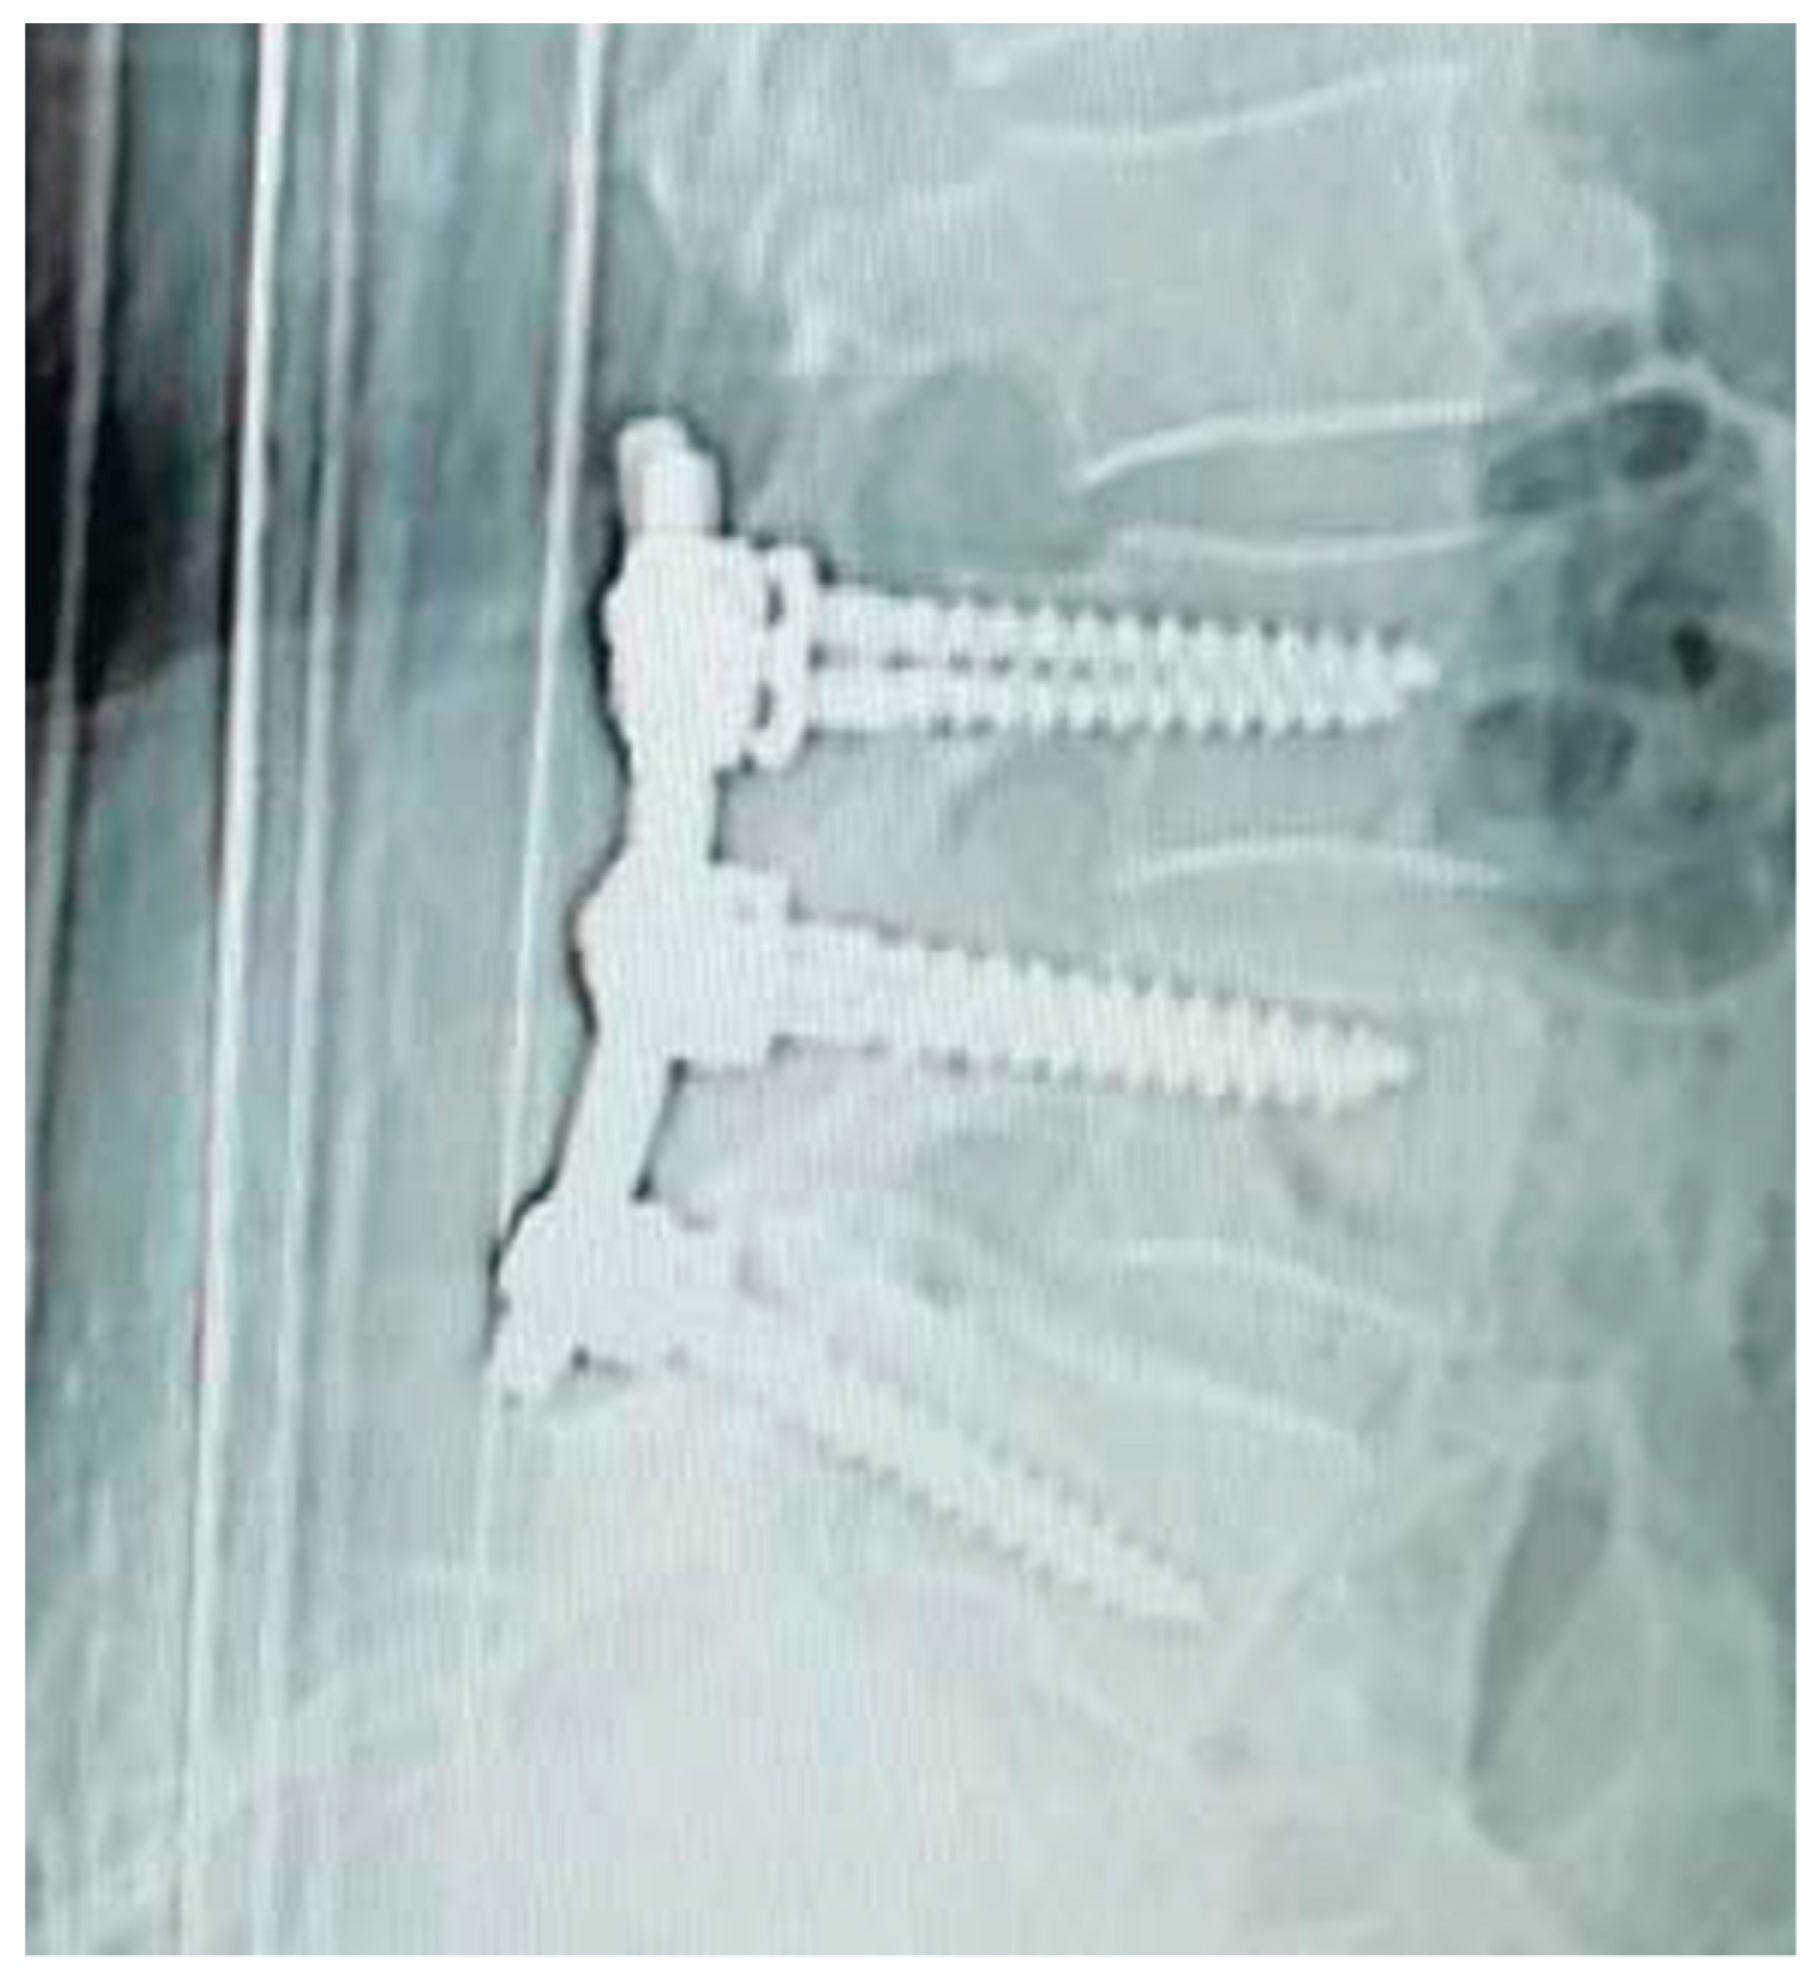

Figure 6, Figure 7, Figure 8 and Figure 9 show examples of pre- and post-operative X-ray shots.

Figure 6. Post-operative sagittal X-ray check—patient code: 2ATL3L4L5110.